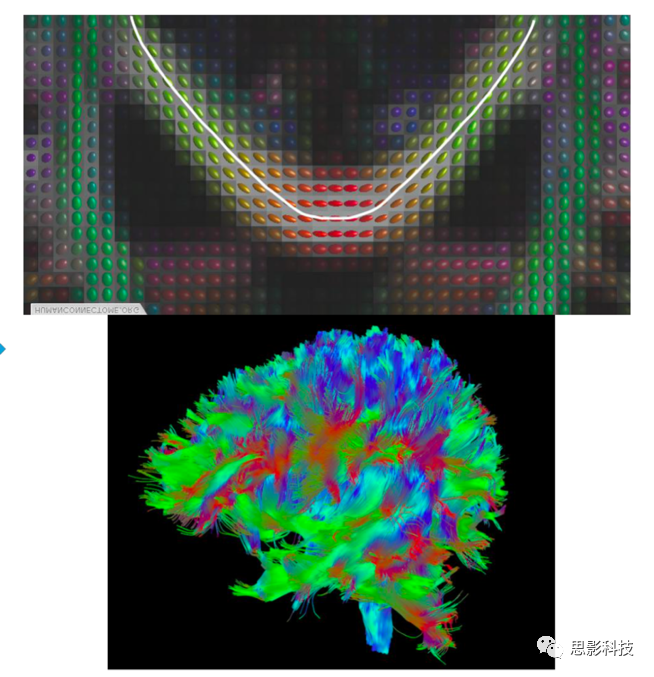

圖例 DTI數據處理流程

1.確定性纖維追蹤    確定性纖維追蹤主要使用FACT、steamline等追蹤方法根據張量主方向以及預設的偏轉角閾值、FA閾值等參數對全腦纖維束進行構建,而后通過設定ROI的方式追蹤特定纖維束,并計算纖維束的數目、平均FA等相關指標。

圖例:全腦纖維束構建